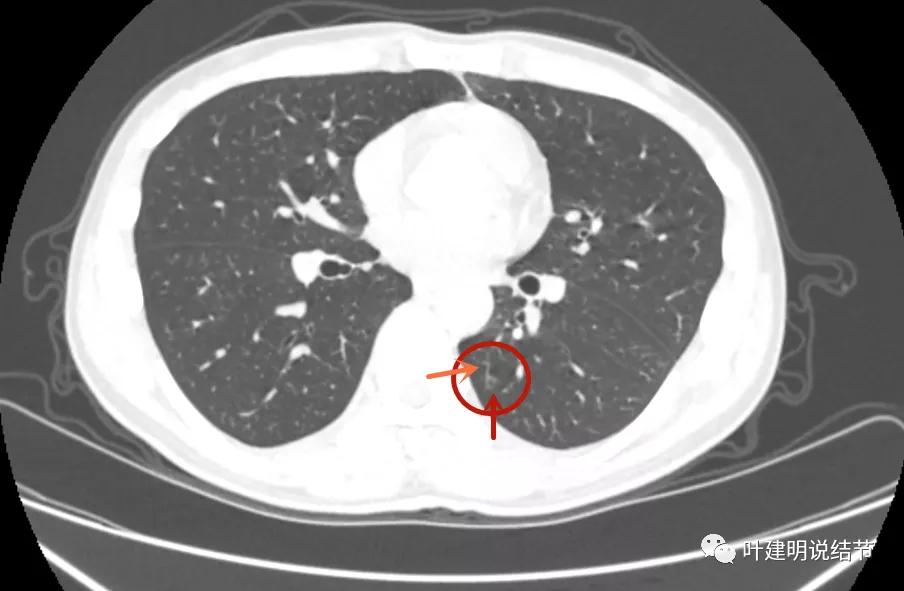

先来看2021年8月的:

病灶1:左上叶结节是混合磨玻璃,但磨玻璃部分密度很低,实性部分密度高,感觉偏散,没有明显收缩力,瘤肺边界模糊不清

病灶2:左下叶极淡的磨玻璃结节,中间似有空泡或偏低密度,但血管似乎有点走向病灶的样子